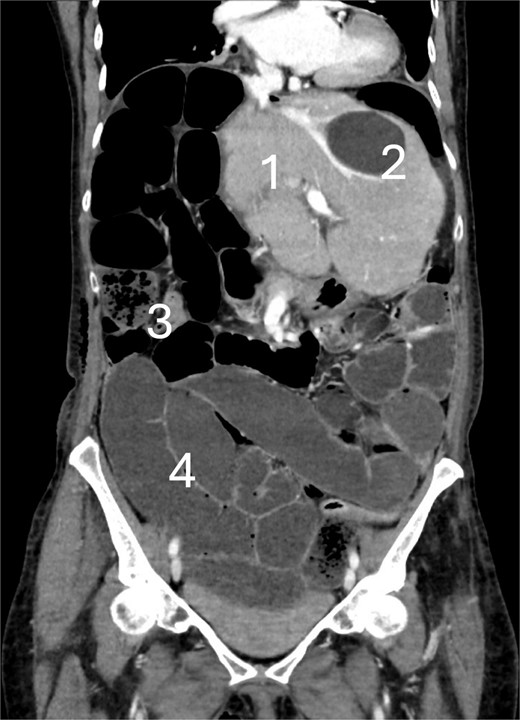

We report on a patient in her 70s with no history of abdominal surgeries, who underwent an elective open right hepatectomy for a large (11 cm) cholangiocarcinoma without signs of extrahepatic metastases. Due to an extensive centrally located tumor, an open resection was performed. The tumor was staged as pT1b. No direct mobilization of the colon was performed. On the fourth postoperative day (POD), a CT scan was conducted due to abdominal distension and absence of defecation, indicating signs of paralysis. On POD 6, the CT scan was repeated because of worsening abdominal pain and lack of clinical improvement, showing mechanical small bowel obstruction at the terminal ileum, and suspicion of cecal volvulus (Fig. 1). The patient underwent emergency laparotomy showing a cecal volvulus (Fig. 2). Intraoperatively, a pronounced mobile cecum was identified, and a right hemicolectomy was performed. Due to sepsis and the requirement for noradrenaline, a primary anastomosis was not feasible, so an end-ileostomy was performed. The patient was transferred to the Intensive Care Unit (ICU) postoperatively. During the postoperative course the patient experienced prolonged paralysis, surgical site infection, bacterial contaminated ascites, and fascial dehiscence. The patient was discharged at POD 42. The patient was doing fine 3 months after surgery.

CT scan at the 6th postoperative day after hepatectomy showing cecal volvulus with: (1) Remnant liver, (2) benign liver cyst, (3) small bowel feces sign, and (4) fluid-filled dilated small bowel.